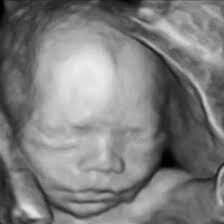

• 3D Ultrasound Tech.

3D Ultrasound Tech.

Kazunori Baba of the University of Tokyo developed 3D ultrasound technology and captured three-dimensional images of a fetus in 1986.